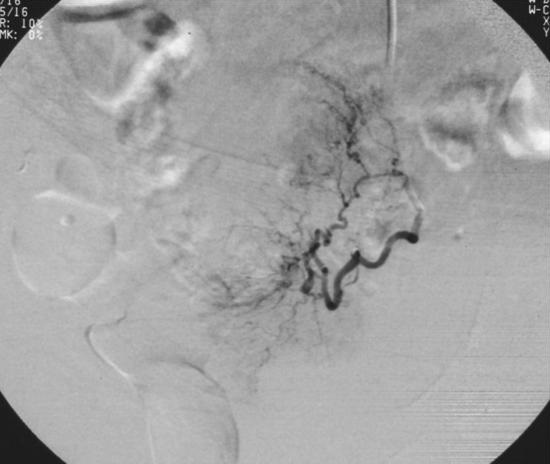

Embolization technique

卵巢动脉